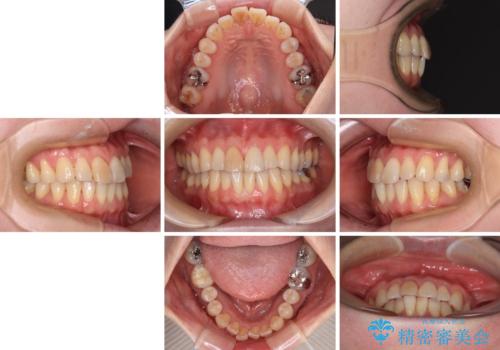

前歯のデコボコをインビザライン・モデレートで矯正治療

- 上下前歯のデコボコを気にして来院された患者様です。

安価なインビザラインパッケージを用いての治療を希望されており、デコボコの程度が中等度であったため、インビザライン・モデレートを用いて矯正治療を行うこととしました。